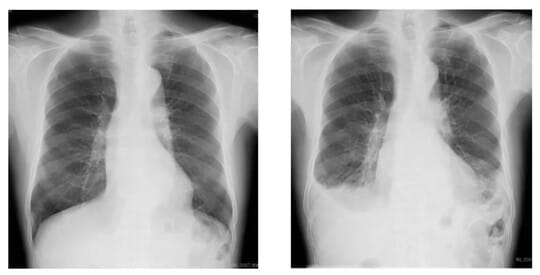

これは心機能の抑制効果が少ないので、心臓に副作用を起こすリスクが非常に低いとされています。しかし、その反面、3%の割合で間質性肺炎を起こすことがわかっています。

![[図表2]「アミオダロン」を服用して、間質性肺炎を引き起こした不整脈患者のレントゲン写真。右写真は白がかっている 提供:東京ハートリズムクリニック](https://ggo.ismcdn.jp/mwimgs/3/0/540/img_30ca116a27b6777850a60e07e44b2391105297.jpg)